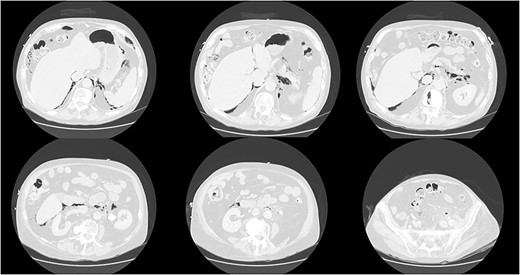

His vitals were stable on presentation. Physical exam was significant for weakness, tachypnea, and wheezing. He had no appreciable subcutaneous emphysema on clinical exam. Workup in the emergency department was remarkable for increased white blood cell count (17.0 K/uL). EKG showed no acute changes and cardiac enzymes were within normal limits. Computed tomography (CT) of the chest, abdomen, and pelvis with contrast was obtained, demonstrating acute sigmoid diverticulitis with extensive retroperitoneal air originating next to the sigmoid colon and multiple small collections of fluid. The pneumoretroperitoneum was continuous with pneumomediastinum and cervical emphysema (Figs 1 and 2). He was diagnosed with perforated diverticulitis and operative intervention was recommended.

CT scan of the chest demonstrating subcutaneous emphysema and extensive free gas in the mediastinum and retroperitoneum.